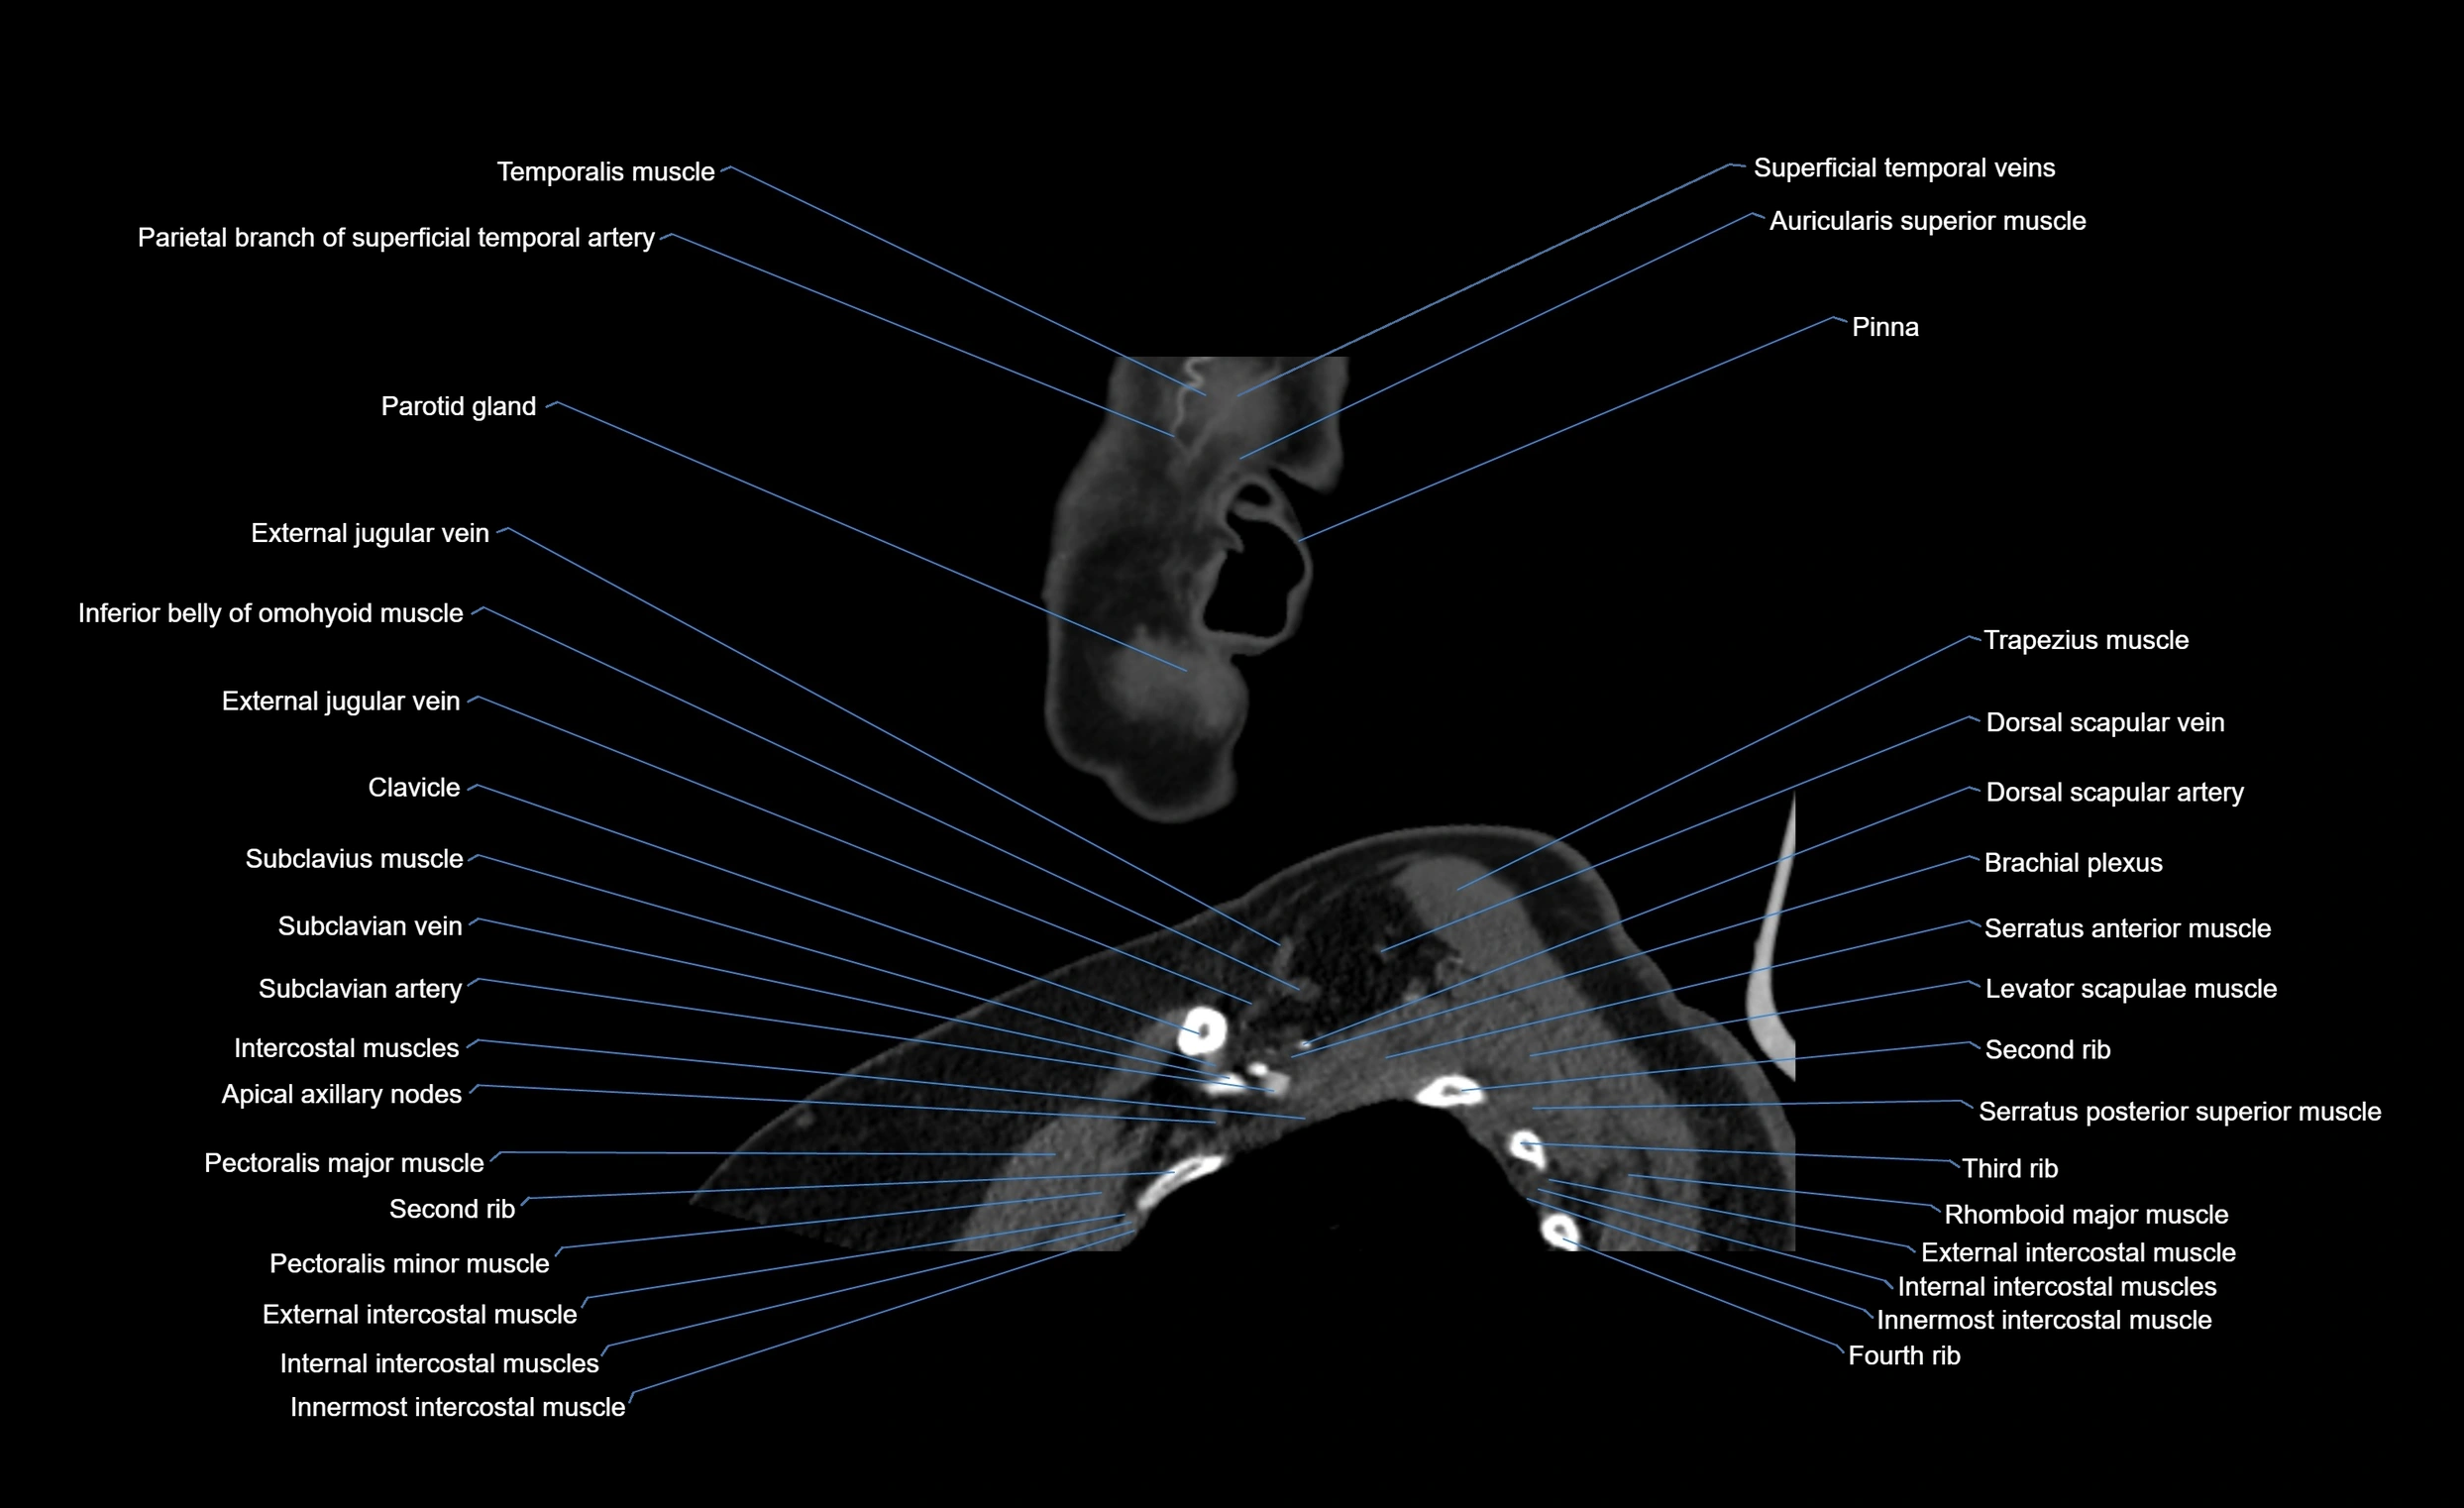

- Clavicle

- Dorsal scapular artery

- Dorsal scapular vein

- External jugular vein

- Inferior belly of omohyoid muscle

- Intercostal muscles

- Levator scapulae muscle

- Pectoralis major muscle

- Serratus anterior muscle

- Serratus posterior superior muscle

- Subclavian artery

- Subclavius muscle

- Brachial plexus

- Rhomboid major muscle